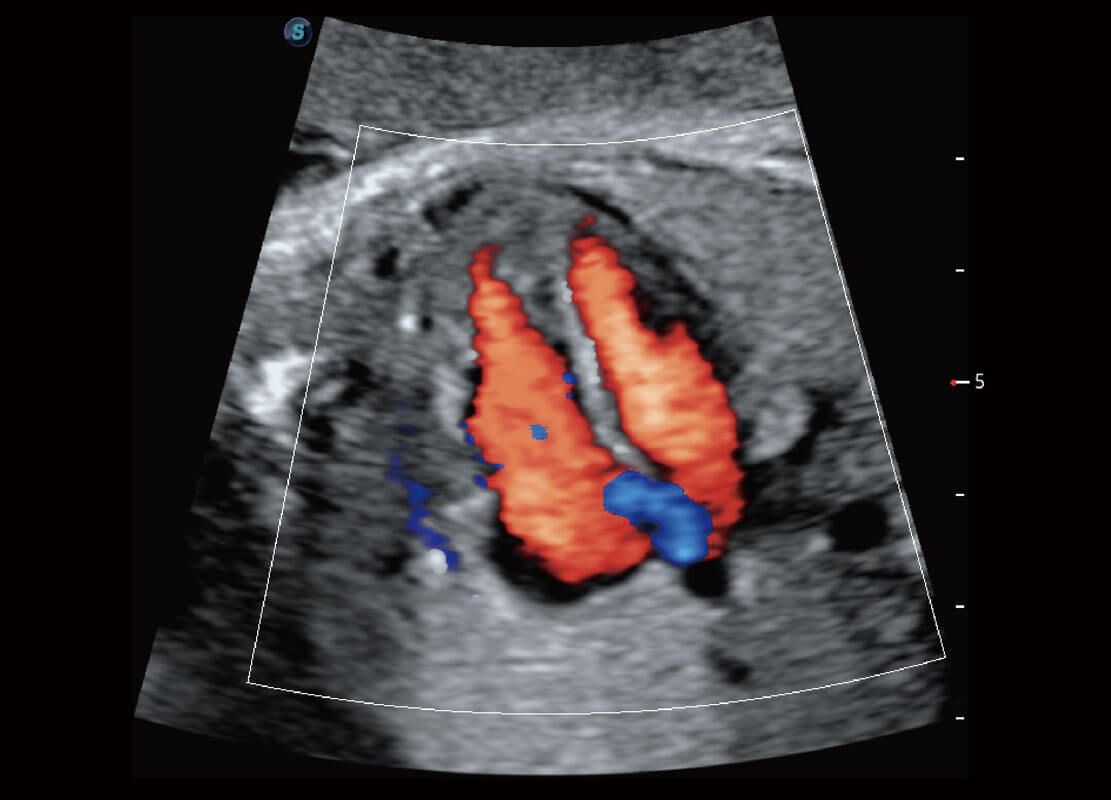

P60在胎兒早孕期超聲篩查中為您帶來(lái)優(yōu)異的圖像質(zhì)量。

早孕-胎心

胎兒體循環(huán)